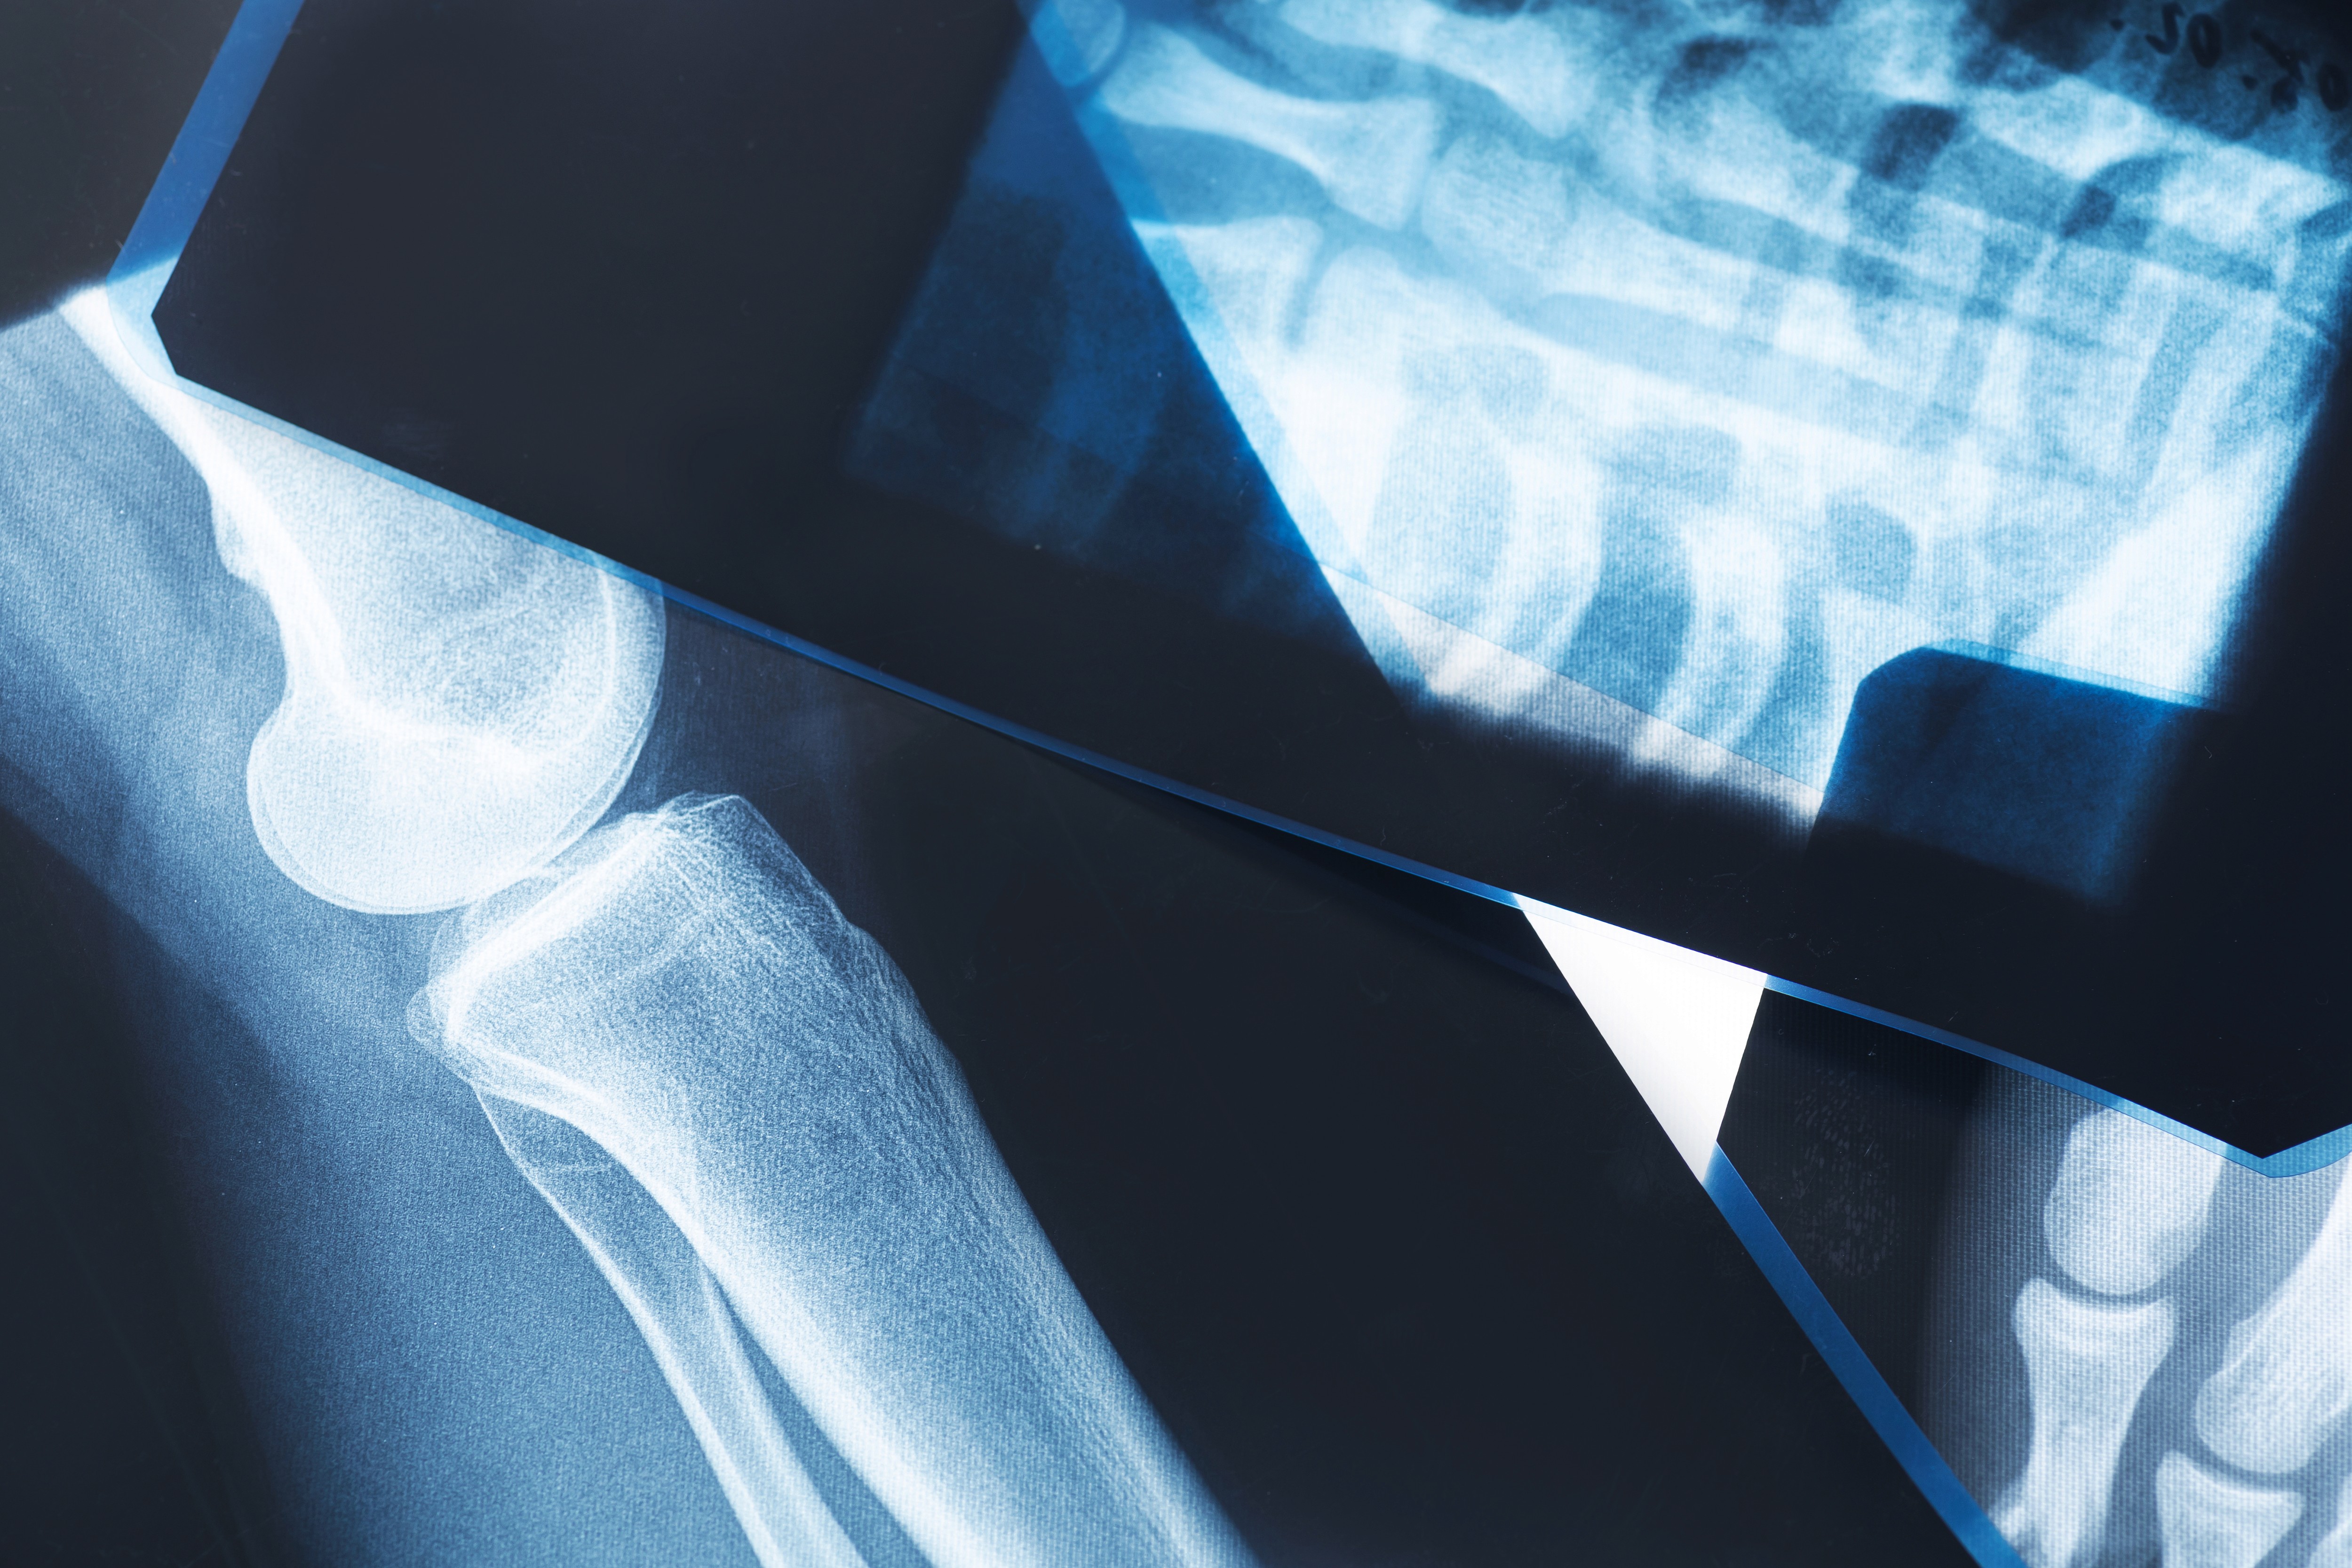

Das digitale Röntgen ist ein bewährtes Verfahren zur schnellen und präzisen Darstellung von Knochen und Gelenken. In unserer Praxis nutzen wir modernste digitale Technik, die im Vergleich zu älteren Systemen eine deutlich reduzierte Strahlenbelastung bei höherer Bildqualität bietet.

Das Röntgenbild liefert unverzichtbare Informationen bei Verdacht auf Knochenbrüche, Arthrose, Verschleißerscheinungen und andere Veränderungen des Skelettsystems. Es ist schnell, schmerzfrei und ermöglicht eine sofortige Diagnose – direkt in unserer Praxis.

Das digitale Röntgen bleibt ein unverzichtbares Werkzeug in der orthopädischen Diagnostik. Es liefert schnelle, klare Antworten bei Knochen- und Gelenkproblemen. Dank moderner Technik ist die Strahlenbelastung heute minimal – und die Bildqualität besser denn je.